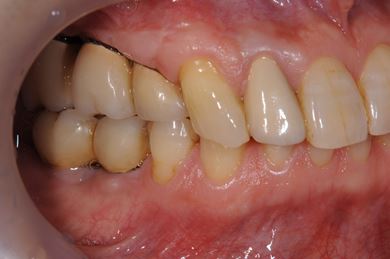

インプラントの症例写真 IMPLANT

骨再生インプラント治療+セラミック治療

| 性別/年齢 | 男性 / 60歳 | ||||||||||||||||||||||||||||||||

| 主訴 | 右上奥歯が動いて痛みがある。 | ||||||||||||||||||||||||||||||||

| 治療方針 | サイナスリフトにて上顎洞を拳上し、骨再生療法を用いてインプラント治療を可能にする。 | ||||||||||||||||||||||||||||||||

| 治療内容 | インプラント5本(サイナスリフト、GBR)、ハイブリッドセラミッククラウン5本、メタルボンドセラミッククラウン1本(メタルボンド用土台1本)、ハイブリッドセラミックインレー、遊離歯肉移植手術 | ||||||||||||||||||||||||||||||||